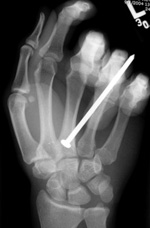

| Nail gun injury |

Left index finger middle phalanx nail gun injury |